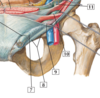

2

2 - celiac trunk with common hepatic, left gastric, splenic arteries

4

4 - right renal artery

6

6 - common iiac arteries

7

37 - internal iliac artery

8

8 - external iliac artery